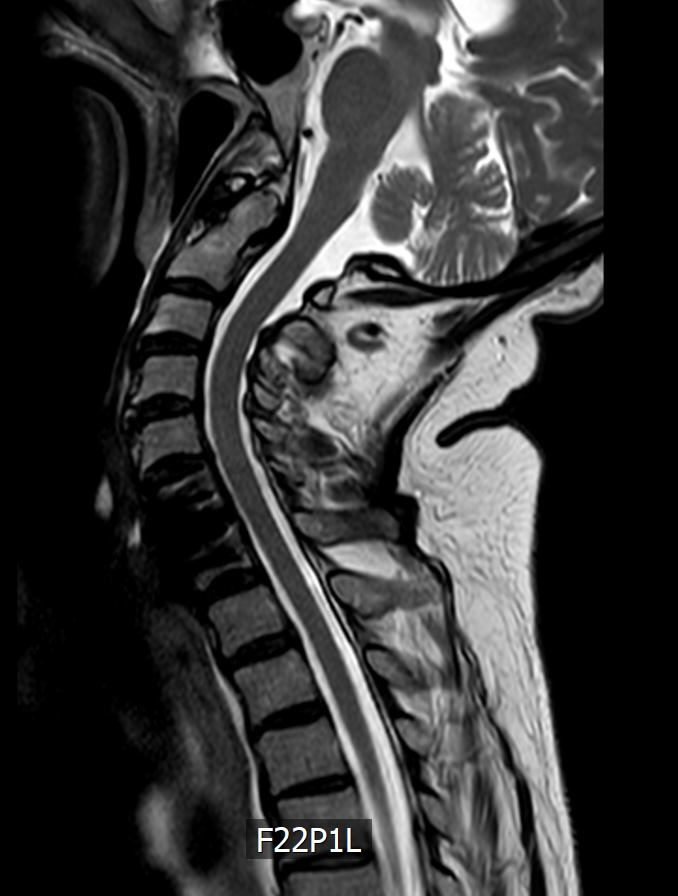

Das MRT zeigt eine 78 jährige Patientin. Schon seit Jahren klagt sie immer wieder über Nackenschmerzen. Seit einem halben Jahr hat sie ein Taubheitsgefühl in beiden Händen. Die Feinmotorik hat deutlich nachgelassen. So ist das Schliessen eines Hemdknopfes und dass Sticken nicht mehr möglich. Das Schriftbild ist kaum noch leserlich. Das Gehen ist sehr unsicher, vor allem bei Dunkelheit und auf unbekanntem Gelände.

Im MRT der HWS sieht man eine Einengung des Spinalkanals in Höhe des 6. und 7. Halswirbelkörpers. Im Spinalkanal verläuft das Rückenmark (dunkelgrau). In der Höhe der Stenose/Bandscheibenvorfalls  zeigt sich ein weisser Fleck innerhalb des Rückenmarkes. Das ist die „Myelopathie“ eine Schwellung bzw. Verletzung des Rückenmarkes aufgrund des Druckes.

Das 2. MRT Bild zeigt die Erweiterung und Entlastung des Kanals nach OP.

Direkt nach der OP waren die Beschwerden erst mal unverändert. Das Rückenmark braucht sehr viel Zeit, um sich zu erholen. Nach 6 Monaten (Zeitpunkt des 2. MRT Bild) war die Symptomatik gebessert aber immer noch nicht vollständig zurückgebildet.